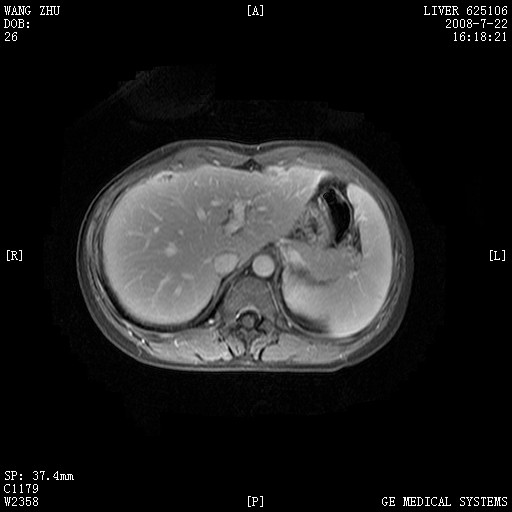

图像有点乱,病灶边缘清楚,可见纤维囊壁,灶旁可见异常灌注,增强显著增强,病灶有早期完全充填,无快退征像,考虑炎性病灶,肝结核可能性大,不知有何病史

肝前外缘见一类圆形囊性病灶,边缘强化,灶周肝为炎性渗出改变,其肝周可见少量腹水,符合炎性病变,病史较长---考虑腹膜结核。肝为外压性改变,脾为动脉期改变。